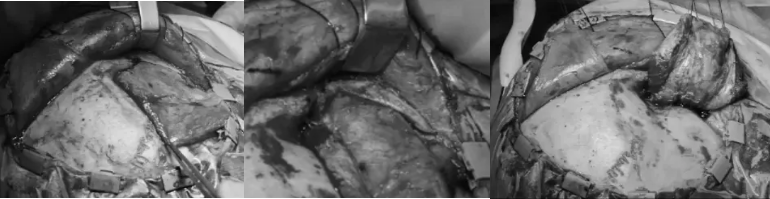

▼使用颧弓入路手术,利用筷子技术神经内镜+显微镜次全切除肿瘤,从海绵窦剥离硬脑膜,切除了浸润的硬脑膜和向颞部延伸的硬膜上脑膜瘤。

▼显微镜下暴露海绵窦外侧壁,注意暴露血管,并进行窦外肿瘤切除。